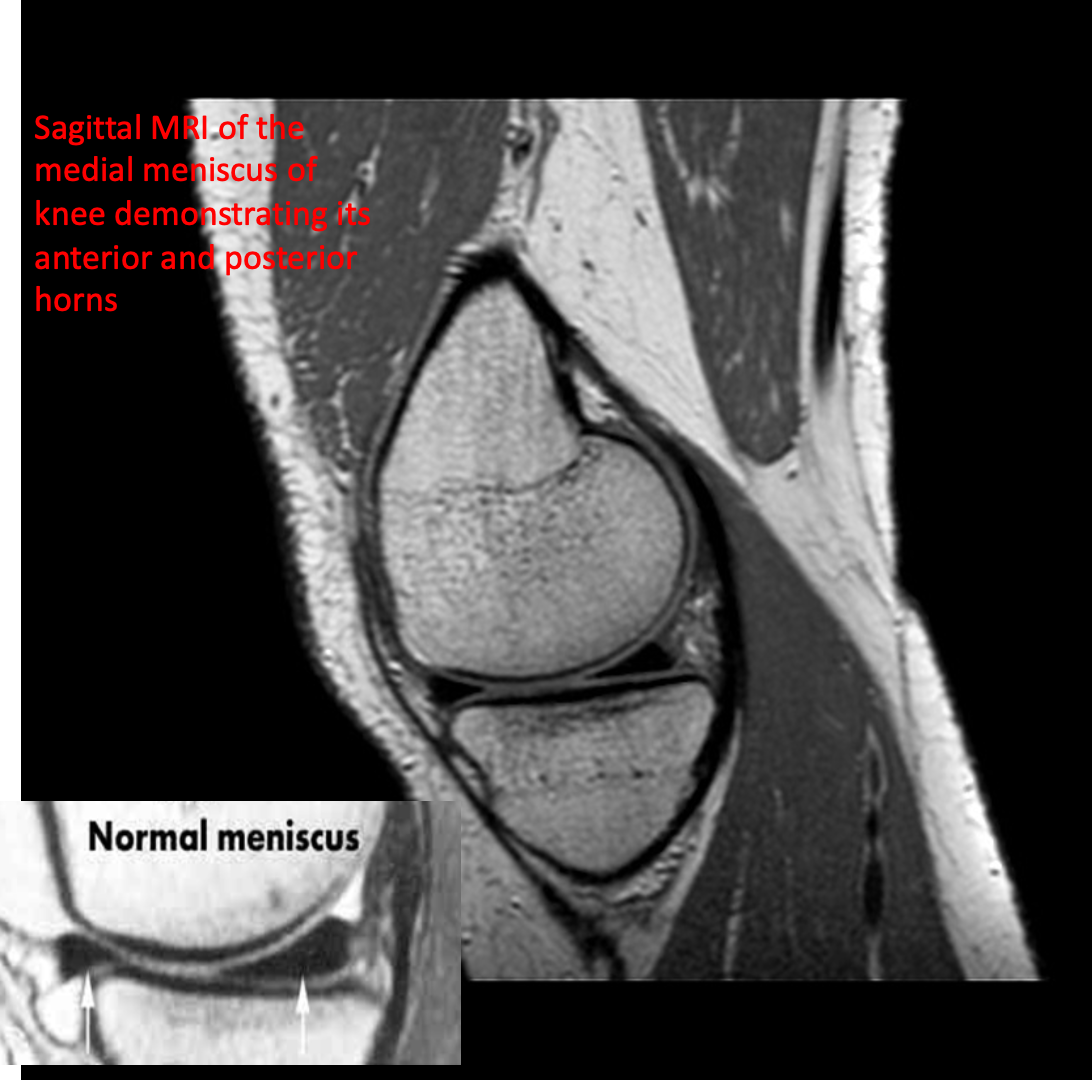

MRI is also very useful for demonstrating injury to soft tissues such as muscle, tendons and ligaments and is particularly useful in knee injuries.

- MRI is the best examination for sports injury.

- Meniscal and ligamentous tears (e.g. in the knee)